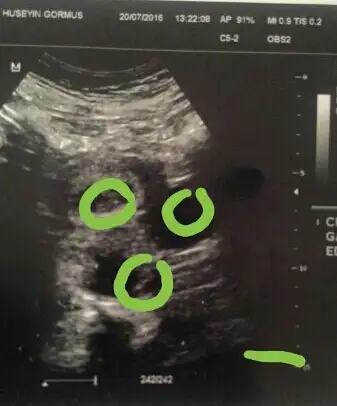

Uc kese goruluyor ama birinde bebis var bakalim digerlerinde bebis gelisecekmi gelisirse ya ikiz ya ucuz geliyor gibi canim

Çok teşekkür ederim,peki ikiz veya üçüz olunca diğerleri sonradan gelişebiliyor mu?Benim hiç fikrim yok ondan soruyorum,bir de diğer keseler niye var anlayamadım,ne olur bilen arkadaşlar varsa bana yardımcı olurmusunuz?bir de o görünen kız mı??Uc kese goruluyor ama birinde bebis var bakalim digerlerinde bebis gelisecekmi gelisirse ya ikiz ya ucuz geliyor gibi canim

Himm belli olur canim daha kucukmus ikiz yada ucuz ikisi dolu bir bos gibi tabi sonradan gelisir bebek haberlerini bekliyorum canim merak ettim :))Bebek 6 hafta

Çok sağol,yarın doktora gidicem hemen,bildiririm,onlar neden boş olsun ki değil mi,o zaman neden kese oluşur ki acaba?Himm belli olur canim daha kucukmus ikiz yada ucuz ikisi dolu bir bos gibi tabi sonradan gelisir bebek haberlerini bekliyorum canim merak ettim :))

ucuncude var sanki yakinlastirip baktim canim doktor kalp atisi alinca soyleyecek belki cnmÇok sağol,yarın doktora gidicem hemen,bildiririm,onlar neden boş olsun ki değil mi,o zaman neden kese oluşur ki acaba?

Eki Görüntüle 1861953 ucuncude var sanki yakinlastirip baktim canim doktor kalp atisi alinca soyleyecek belki cnm Eki Görüntüle 1861955